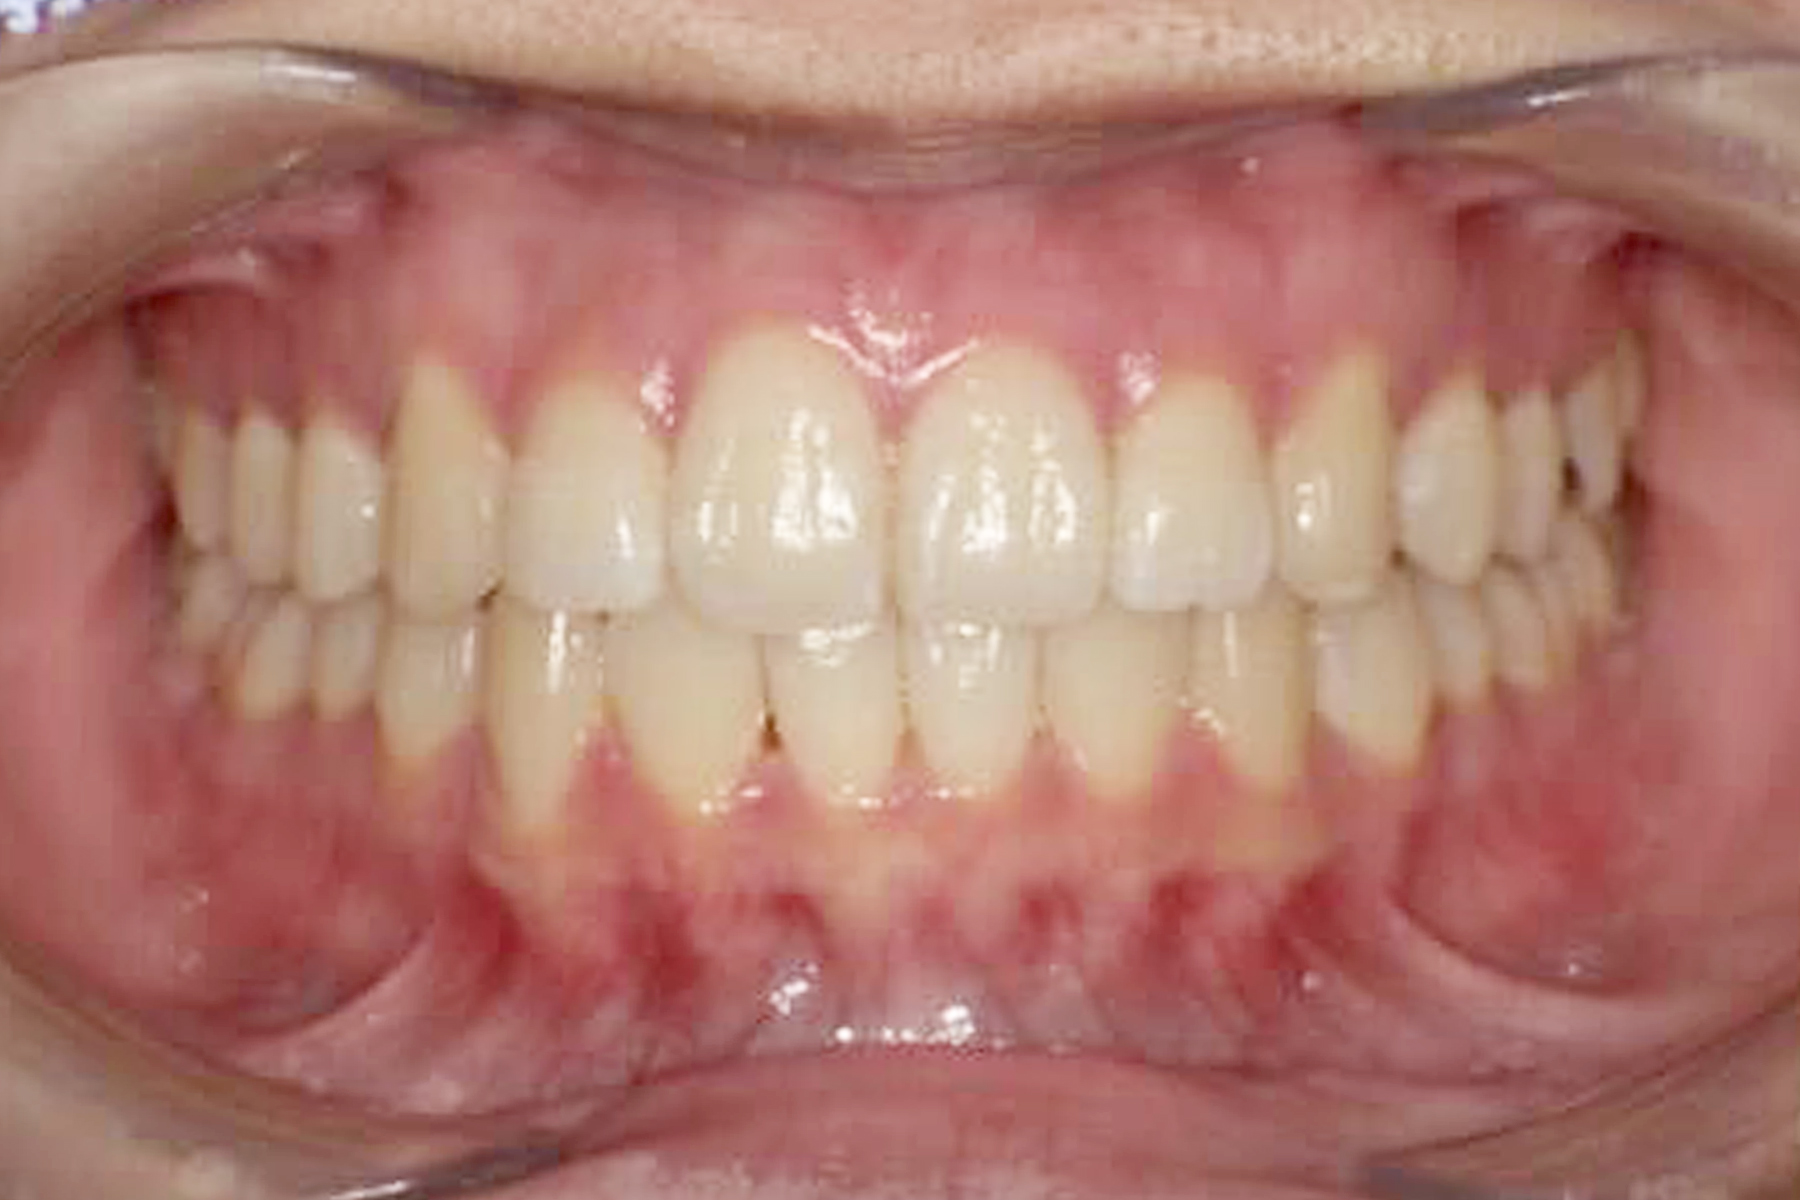

Case.1

BEFORE

AFTER

| 担当医 | 林 大貴 |

|---|---|

| 主訴 | 歯並びを直したい |

| 期間 | 約6ヶ月 |

| 費用 | 550,000円 |

| 治療内容 | マウスピース矯正 |

| 治療に伴うリスク | 動的治療後、保定装置を決められた期間確実に装着しなかったり した場合後戻りが起こる可能性があります。 |